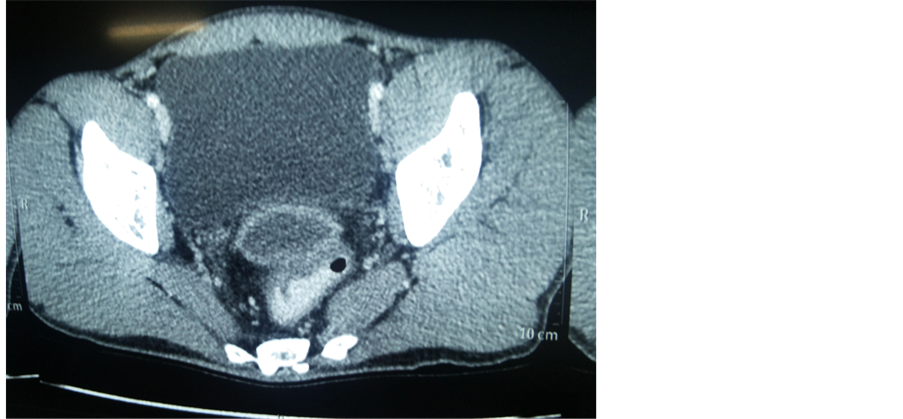

The second case of pelvic hydatid disease was asymptomatic, and was discovered by chance while examining a 59-year-old man for benign prostatic enlargement. Because he was asymptomatic, patient was kept under observation and was put on albendazole. He is asymptomatic in follow up period of six months.

Figure 5. CECT of 2nd case showing retrovesical pelvic hydatid cyst.

In our 1st case, cyst was occupying whole of the pelvis with pressure on pelvic part of both ureter resulting in bilateral hydronephrosis with nonfunctioning right kidney. Surgery was conducted in 1st case and 2nd case was kept under observation and both patients were given a course of albendazole. The pathology confirmed the diagnosis in the first case and radiological imaging modality confirmed the diagnosis in the second case. Both patients are now asymptomatic with follow up to six months.